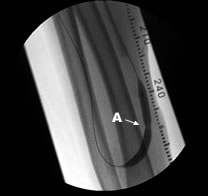

Aシャント血管瘤 Bシャント吻合部

シャント血管がこぶ状に膨らんだ状態をシャント血管瘤といいます。人工血管内シャントにも仮性血管瘤という同じような瘤が出来る場合も有ります。血管瘤は、こぶの皮膚が薄くなったり、痛み、感染、急速に拡大したりすれば手術が必要となります。